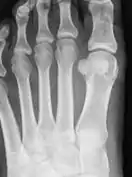

Braquimetatarsia (del griego brachys, corto, y metatarsia, relativo al metatarso) o metatarso hipoplásico es una condición médica en la cual existe uno o más metatarsos anormalmente cortos.[1] El tipo más común de braquimetatarsia es la que afecta al primer metatarsiano. Esta es conocida como Pie de Morton

Esta enfermedad puede deberse a un defecto congénito o puede ser adquirida.[1] Generalmente afecta al cuarto metatarso y está presente en ambos pies (braquimetatarsia bilateral). En caso de que el defecto esté presente en más de un dedo se le denomina braquimetapodia.[5] En caso de que el metatarso afectado sea el primero, esta malformación se conoce como síndrome de Morton. Frecuentemente, genera un inconveniente desde el punto de vista estético e incluso causa otros problemas como metatarsalgia, callosidades o dificultad para calzarse. Existen varios procedimientos médicos para tratar esta condición.[1]